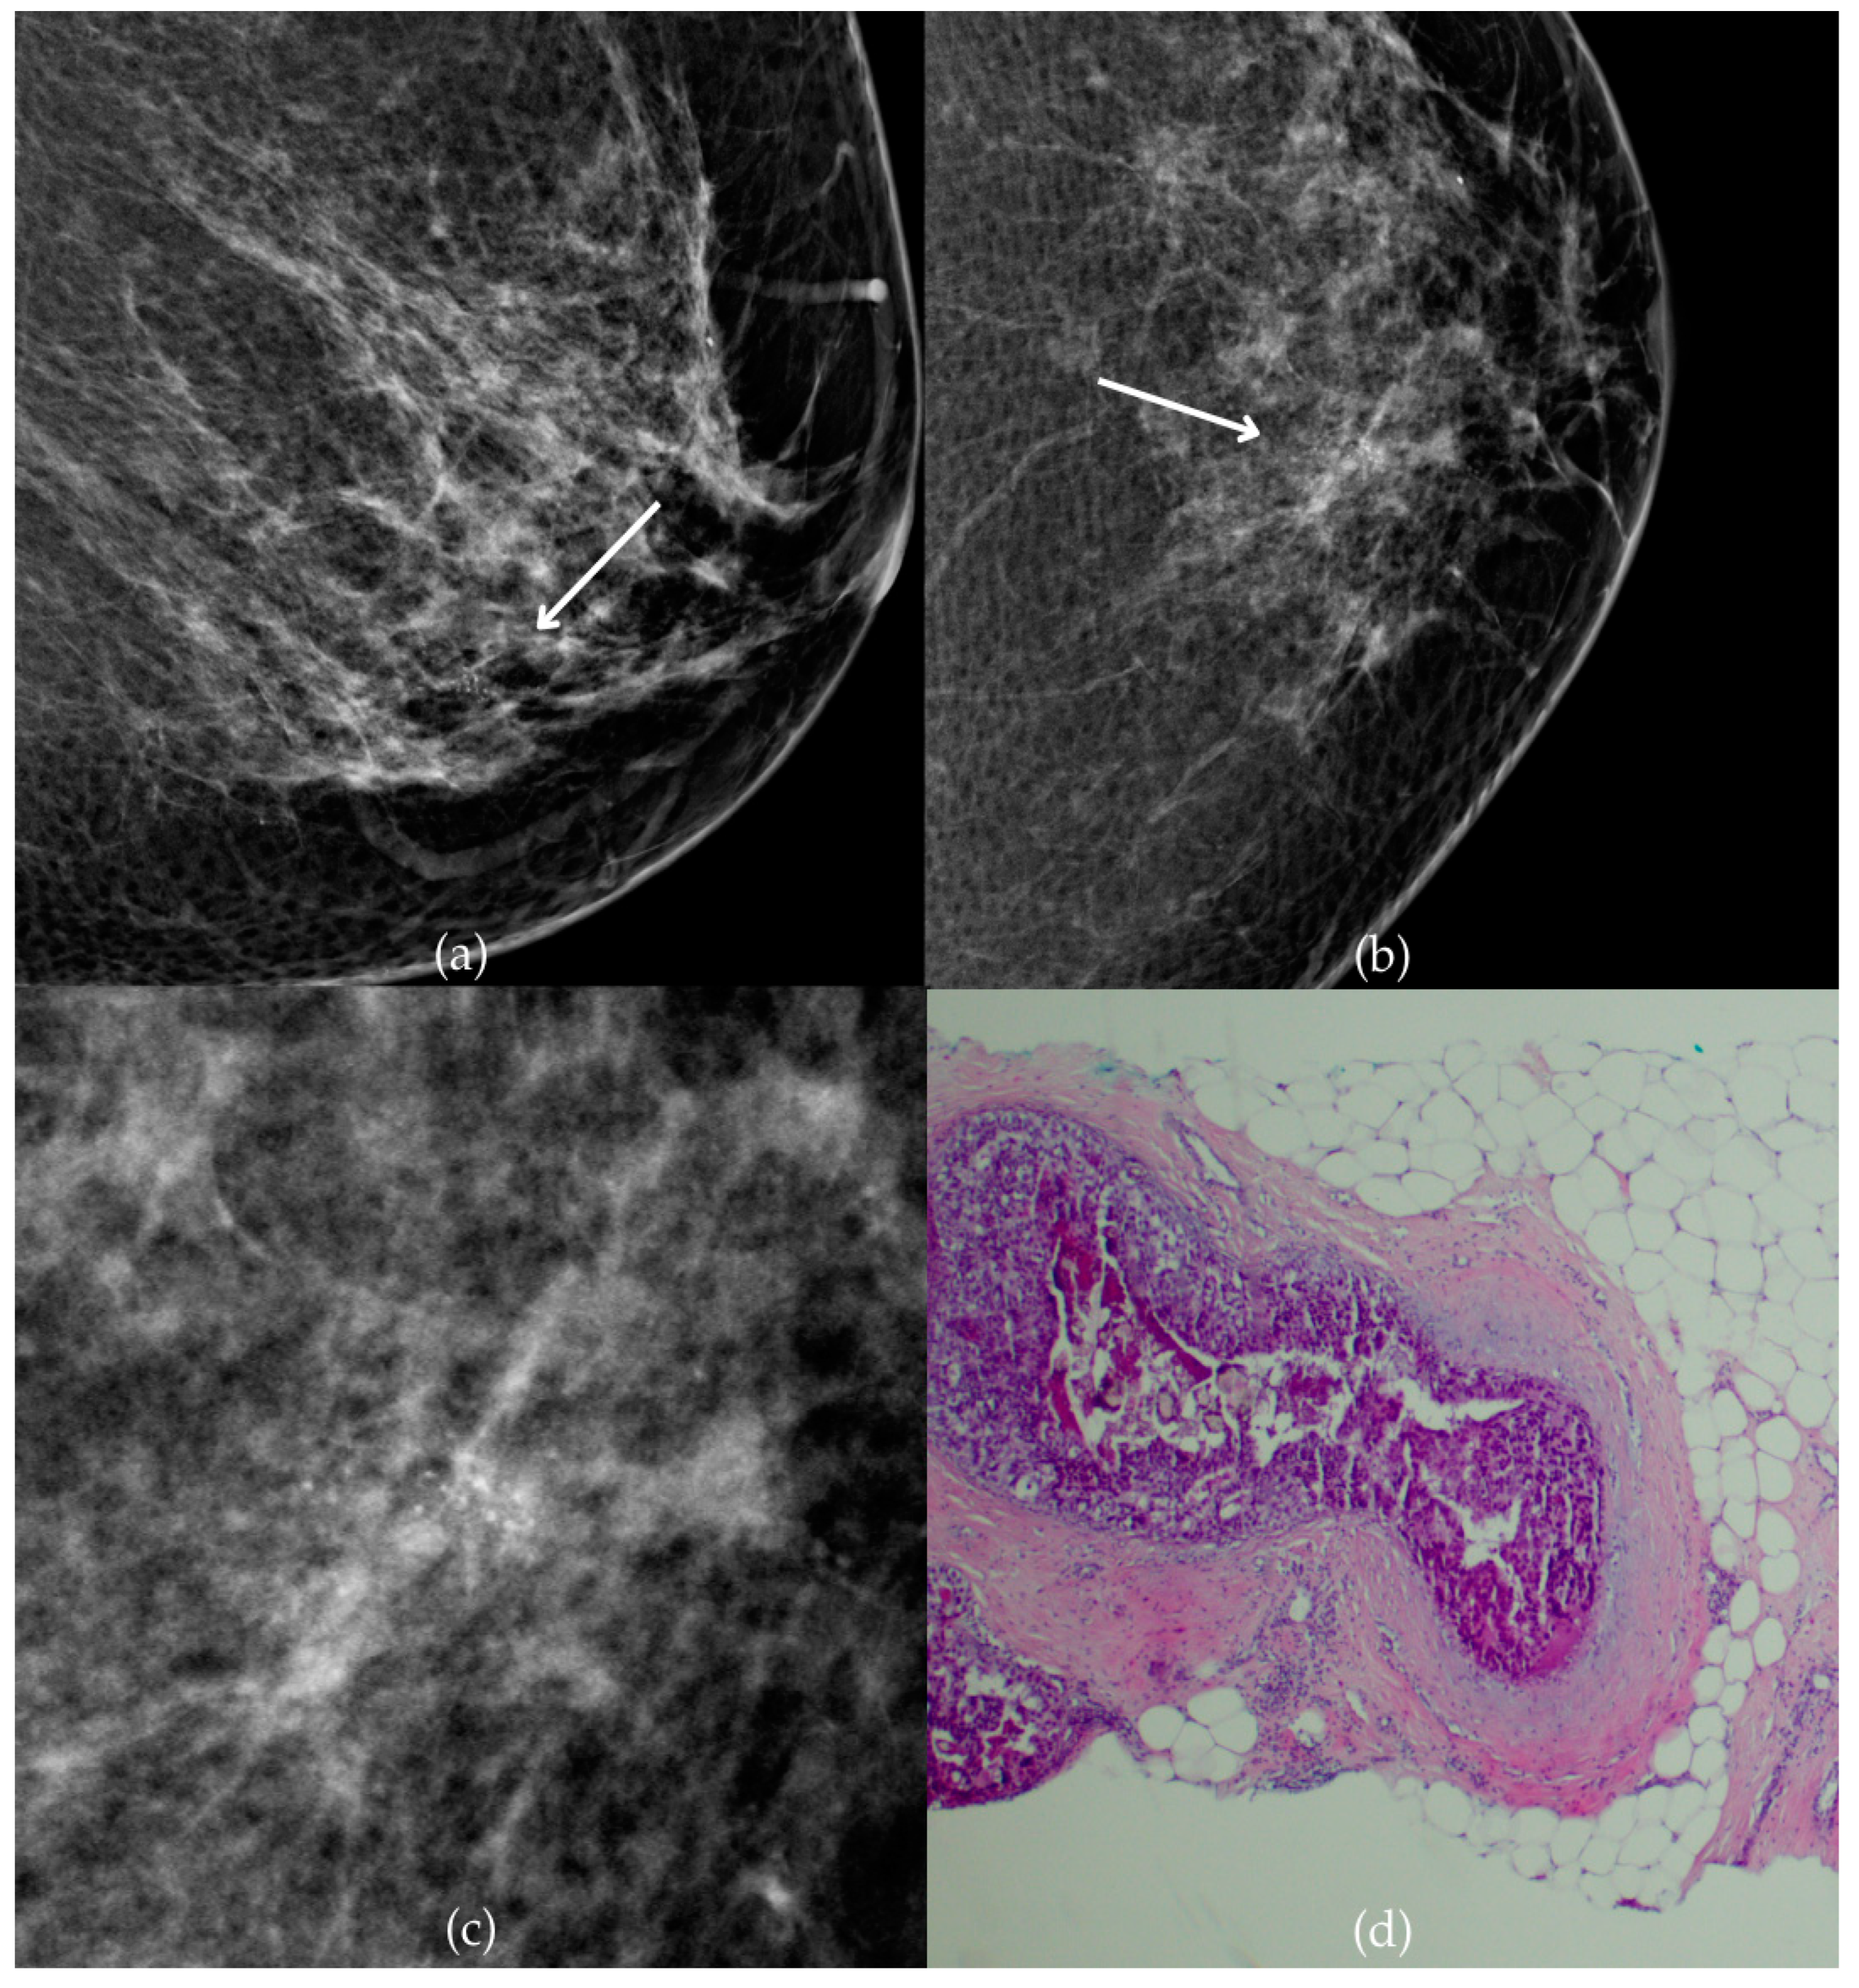

Figure 1 presents mammographic and histopathological images of a 74-year-old patient. The mammogram of the right breast shows grouped coarse heterogeneous and fine pleomorphic calcifications in the upper outer quadrant, classified as a BI-RADS 4 finding. Given the suspicious nature of these findings, a biopsy was performed. A tissue analysis confirmed the presence of a DCIS (category B5a). The patient underwent quadrantectomy, and the postoperative pathology confirmed the diagnosis. At the most recent follow-up, conducted one year after the initial diagnosis, the US examination was classified as BI-RADS 2, indicating benign findings.

Figure 1.

Ductal carcinoma in situ (DCIS). (a) Mediolateral oblique (MLO) mammography view; (b) craniocaudal (CC) mammography view of the right breast showing grouped coarse heterogeneous and fine pleomorphic calcifications (marked with arrows) in the upper outer quadrant. (c) Magnified mammographic image of grouped coarse heterogeneous and fine pleomorphic calcifications. (d) The histopathological image of the biopsy sample reveals the characteristic features of DCIS (HE staining; 40× magnification).